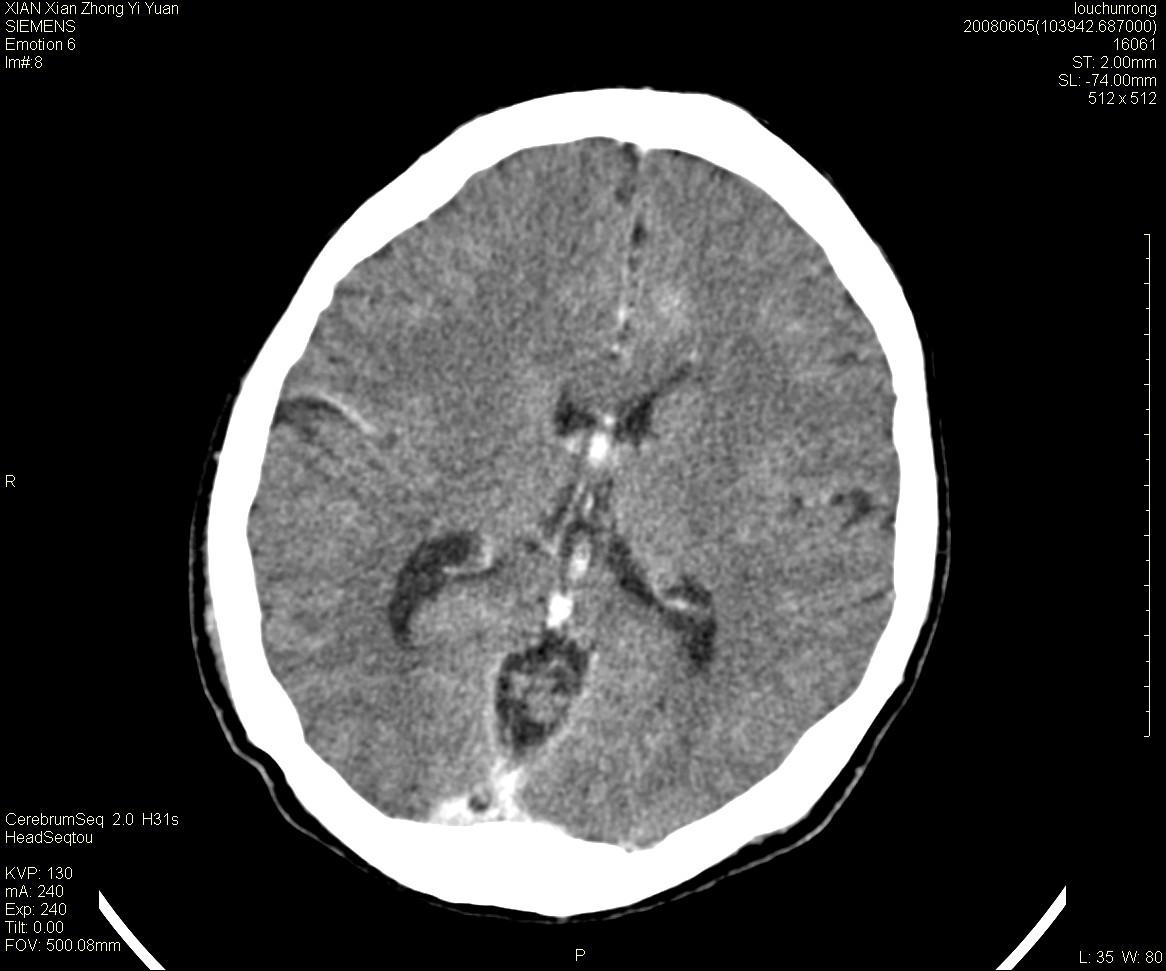

标题: CT13860:F52Y,,头外伤致头晕半天,以前无不适。 [打印本页]

标题: CT13860:F52Y,,头外伤致头晕半天,以前无不适。

层厚2mm。

大家看左额叶大脑镰旁高密度影

两侧脑室体部距离增宽,胼胝体发育不良?

中线附近、枕叶近枕骨处及脑内多发点条状强化影,考虑血管异常?

侧脑室前角变形、变窄,考虑侧脑室粘合;余未见明显异常。